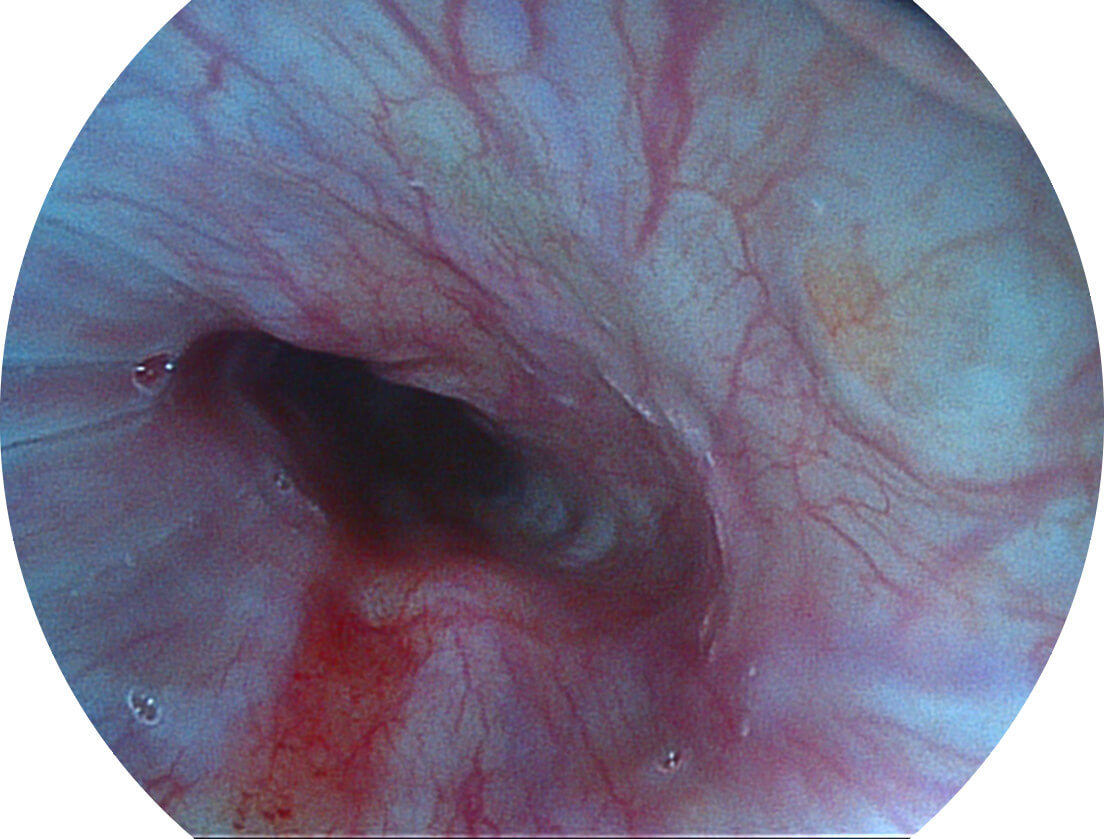

Spectral Focused lmaging, SFI

图像具有高亮度、高黏膜血管颜色对比度的特点,且不改变粘液、食物残渣、粪便的基本颜色,可在中远景下进行观察,助力消化道早期疾病的诊断。

采用光路合束技术,光谱自由度高,实现了更丰富的照明模式,染色模式SFI及VIST,从远景到近景,助力消化道早期疾病诊断。